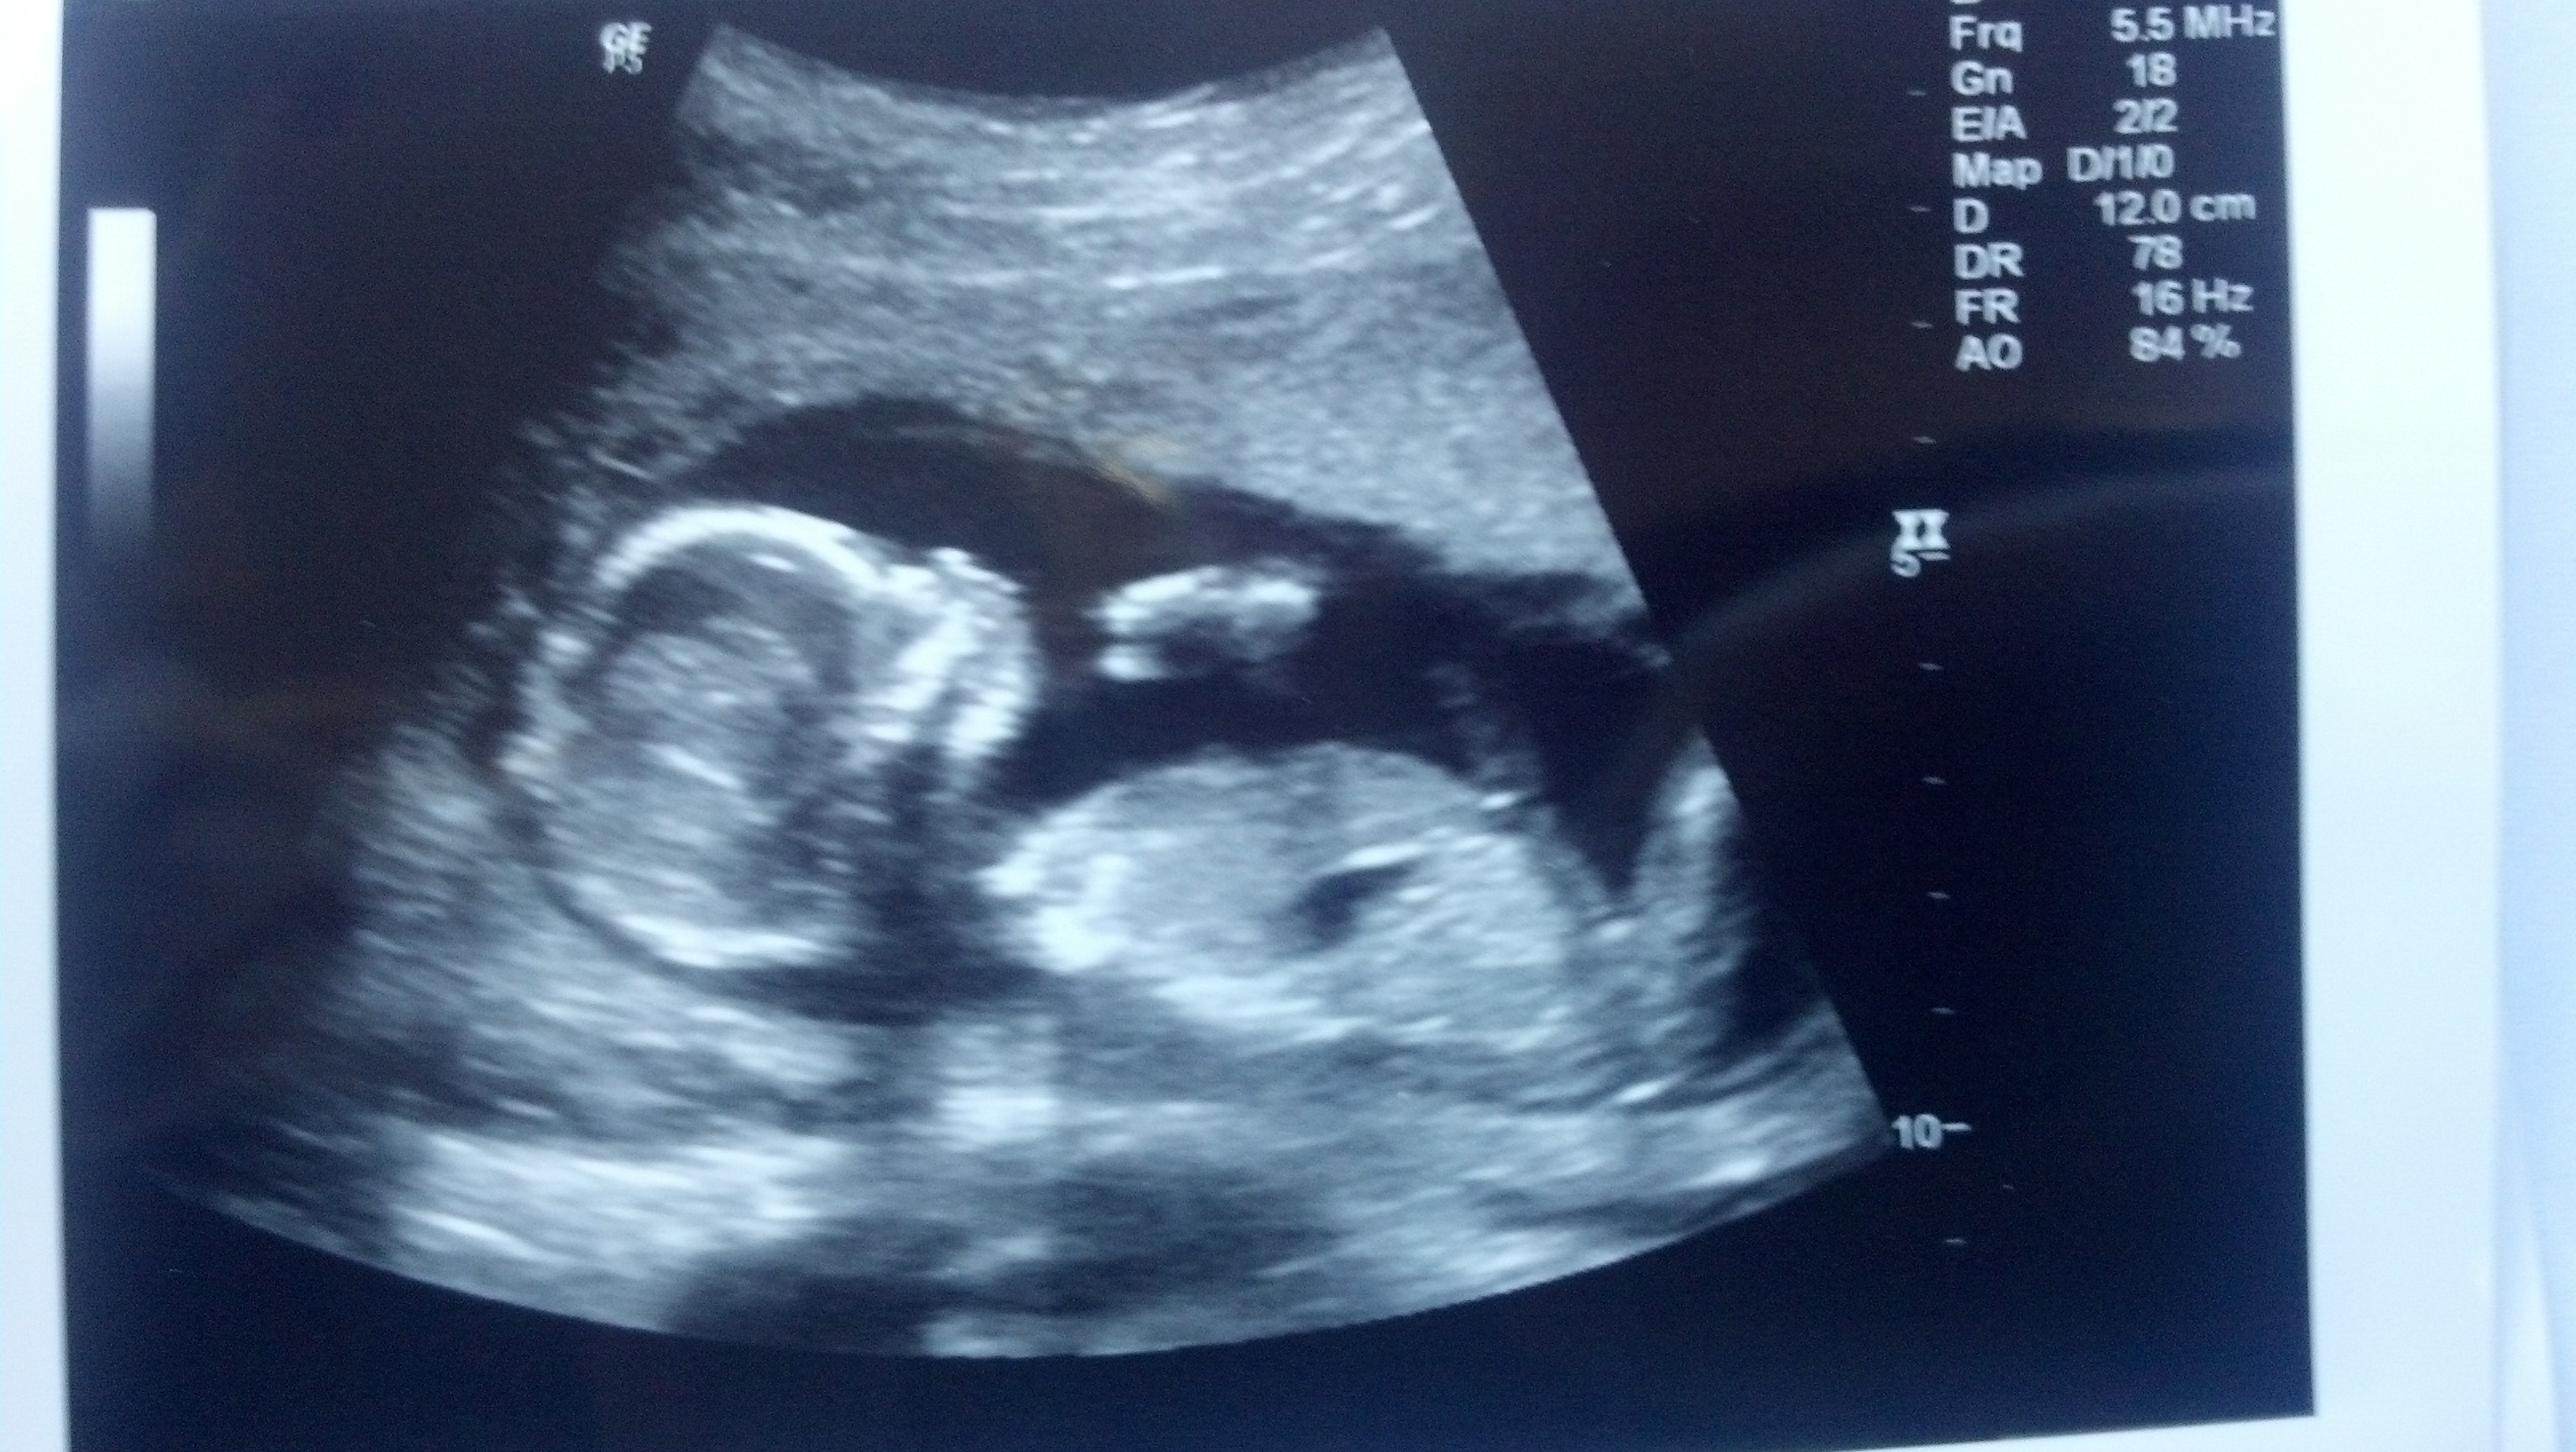

Had my re scan today for gender and i found out nothing! 1st scan moving so much with only water. this time water and pepsi and baby was calm but legs still closed! I schedule my 3D for this Saturday but how if baby would open then, would they get baby to open wide this time??Attachment 13075